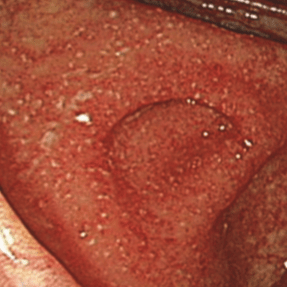

В клинической практике нередко встречается так называемая «сверхтяжелая» или «крайне тяжелая» атака ЯК, характеризующаяся

Сверхтяжелая форма ЯК может быть молниеносной (развивается у пациента без предварительного анамнеза язвенного колита) и внезапной (развивается после длительного анамнеза язвенного колита).

Эндоскопически сверхтяжелая форма язвенного колита характеризуется глубокими (до мышечного слоя) обширными язвенными дефектами, окруженными инфильтрированной слизистой оболочкой. Воспалительный процесс может быть настолько выраженным, что слизистая оболочка может быть представлена сплошной язвенной поверхностью с островками инфильтрированной слизистой оболочки.